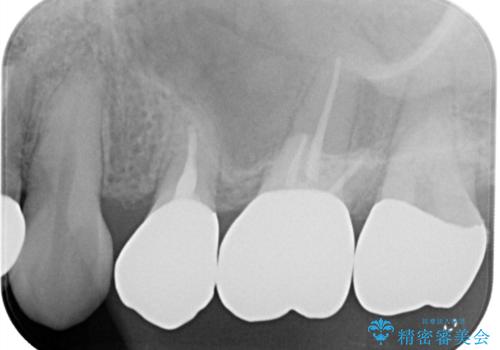

- 二次う蝕が心配という主訴で来院された患者さんです。

保険のメタルインレーは腐食しやすかったり、適合があまり良くなかったりで二次的にう蝕がインレー下で広がってしまうことが多々あります。

メタルインレーを除去したところ、残存歯質量が少なく破折のリスクを説明し、ゴールドクラウンでのやり替えとなりました。